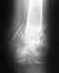

перелом с вывихом стопы

каков будет прогноз

Смотря какой перелом, какой вывих, как лечили...